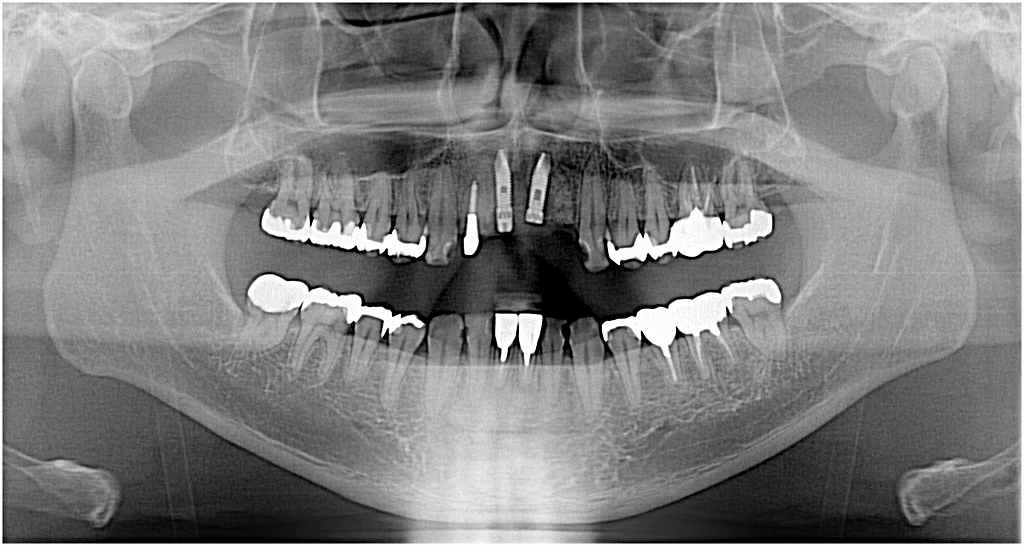

骨幅が狭いために骨を若木骨折させて広げて埋入しています スプリットクレフトテクニック

骨吸収がひどくここは骨造成を行います

欠損部にインプラントを埋入していきます

右上1番は抜歯即時インプラントを埋入しています

このように2本、インプラントを埋入しています

インプラントによる延長ブリッジ予定にしています